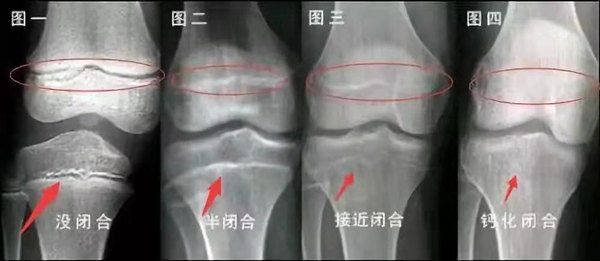

未成年時隨著年齡的增加骺軟骨端不斷骨化,骨骼就不斷增長。當(dāng)骨骺線完全閉合時骨骼就停止生長,個子也就不再增長了。一般骨骺端完全閉合的年齡是18~20歲左右。

骨骺線提前閉合最多見的情況是性早熟,而這也是很多醫(yī)生專家建議孩子進行骨齡測量的原因之一。另外,在兒童時期大量補鈣也會使骨骺端提前過早閉合。

一般來說,女孩的骨齡超過14歲,男孩的骨齡超過16歲,這時其骨骺線已接近閉合,基本沒有長高的機會了。

因此,越早了解骨骺線閉合情況,越早干預(yù),孩子長高的可能性越大。